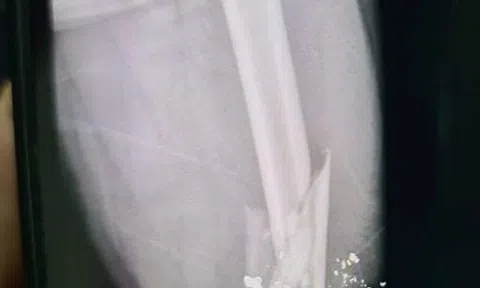

Hà Tĩnh: Mâu thuẫn trong buổi nhậu, người đàn ông bị bắn gãy xương đùi

Do mâu thuẫn trong buổi nhậu, Phan Công Hòa (SN 1981, trú thôn Hiệu Châu, xã Kỳ Châu, huyện Kỳ Anh) đã xách súng bắn bạn nhậu gãy xương đùi.